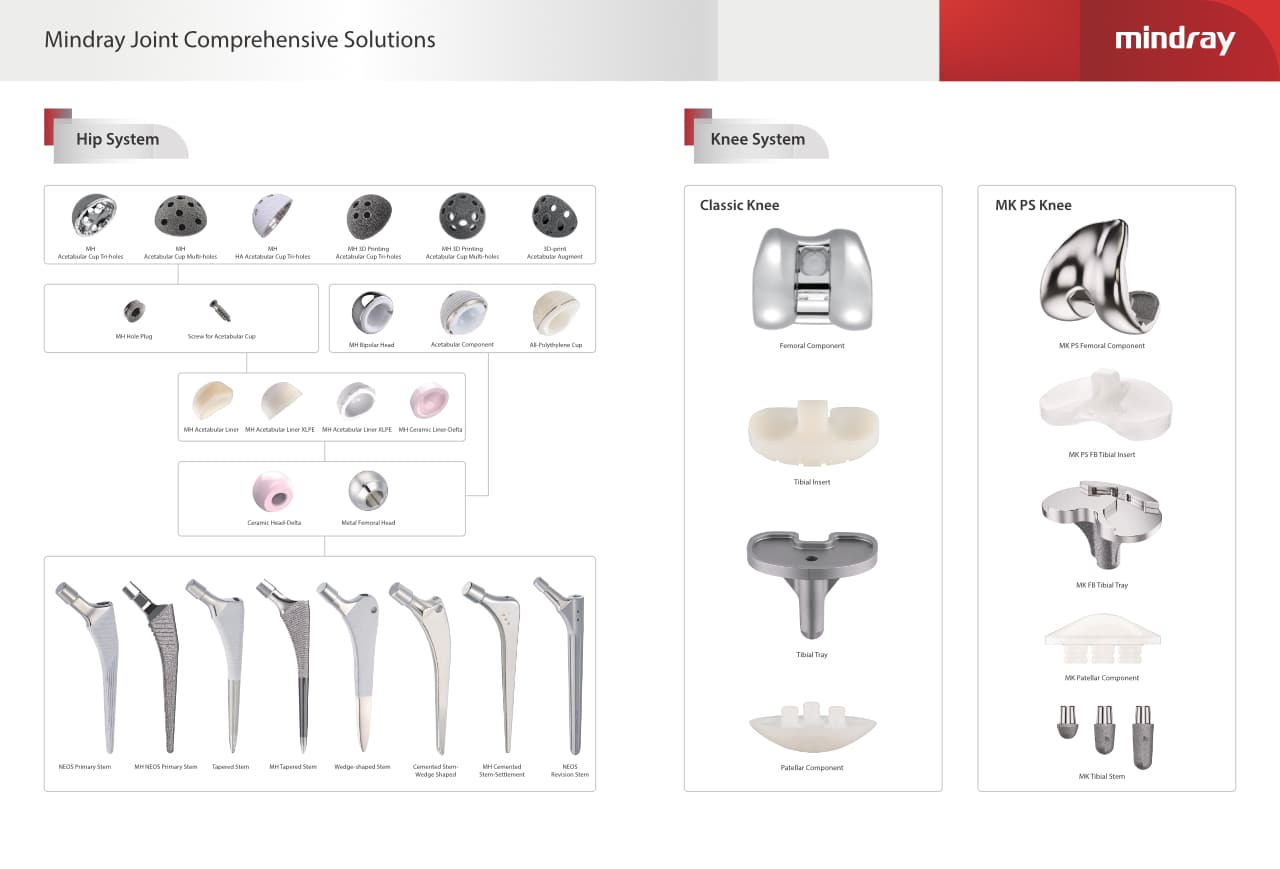

Nuestros productos de artroplastia abarcan dos grandes soluciones para las articulaciones de cadera y rodilla, incluyendo el reemplazo articular primario y de revisiĂłn, segĂșn el tipo de cirugĂa. Los productos de artroplastia de Mindray Ortopedia heredan las caracterĂsticas clĂĄsicas de eficiencia y estabilidad.